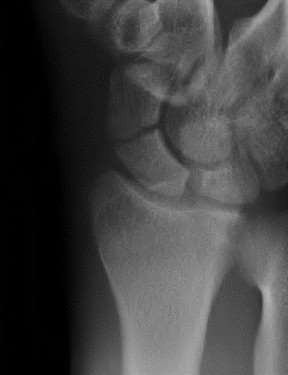

A 22-year-old male falls onto an outstretched hand and sustains a displaced fracture through the proximal pole of the scaphoid. Avascular necrosis of the proximal pole is highly likely due to the disruption of its primary vascular supply. Which vessel provides this critical retrograde perfusion?

Correct Answer: Dorsal carpal branch of the radial artery

Explanation:

The primary blood supply to the scaphoid is from the dorsal carpal branch of the radial artery, which enters the dorsal ridge of the scaphoid at the waist and courses proximally. This retrograde blood flow makes proximal pole fractures highly susceptible to avascular necrosis and nonunion. The superficial palmar branch provides a minor supply (about 20%) to the distal pole.